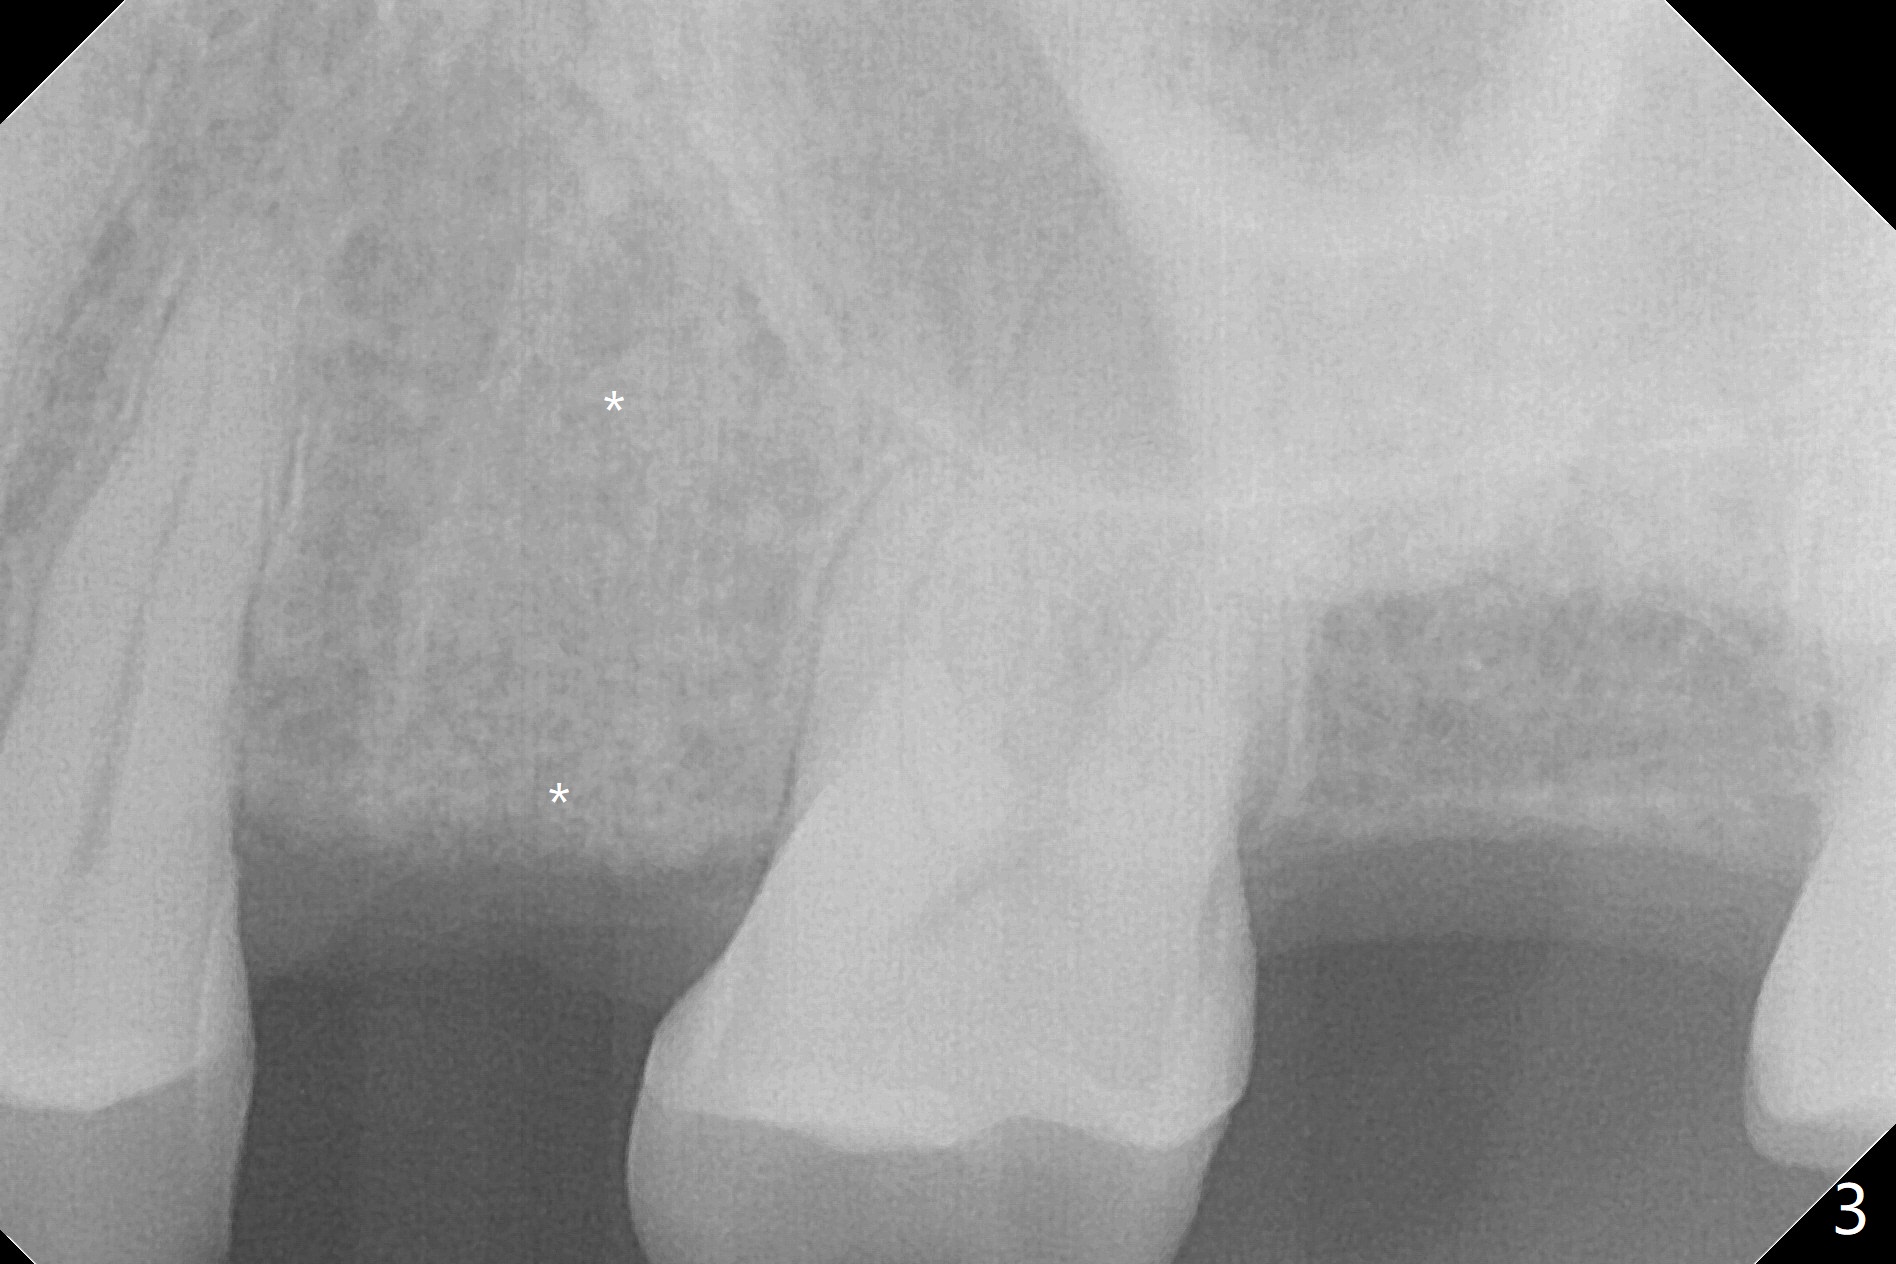

A 65-year-old man cracks 3 teeth in ~2 years (Fig.1,2 (#4,13,15)). The tooth #4 is symptomatic after RCT (Fig.1); it appears that the buccal canal is incompletely filled (data not shown). In fact an exam 1 month later shows that the symptomatic tooth is #2 (crack), while #4 is salvageable (Fig.8). The tooth #13 has palatal subgingival fracture with severe pain (Fig.2 with palatal defect). In fact the title of this case is incorrect). After extraction, allograft is placed (Fig.3 *) with 6-month membrane. In fact the bone graft is not packed into the apex of the socket; a condenser should have been used. The patient returns 3 days postop before leaving abroad. The 6-month membrane remains in place (Fig.4), while the ridge at #15 is minimally atrophic (Fig.5). The coronal lamina dura becomes indistinct 5 months postop (Fig.6). The bone graft remains in the socket. The distoapical portion of a 4x11.5 mm implant may be in the sinus (Fig.7).